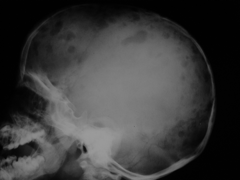

Qual o sinal radiológico de uma fratura craniana com afundamento? Quando ele é visível?

Radiopacidade da linha do afundamento, devido a sobreposição óssea.

Visível na incidência paralela ao plano da fratura.